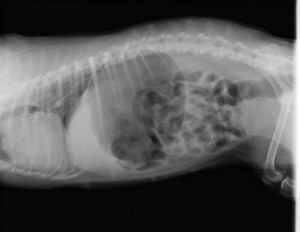

こんにちは 上野の森どうぶつ病院 の諌山です。 本日は胃拡張・胃捻転症候群という病気について。 と、いうのも先…